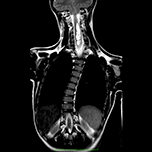

我們是一家位於西班牙巴塞隆納的國際專科醫療中心,不設分院,專注於精準且高品質的醫療照護。我們採用微創手術從病因治療Arnold-Chiari I型症候群、特發性脊髓空洞症與脊柱側彎等相關疾病,致力於為來自世界各地的患者帶來更安全、更有效的治療選擇。